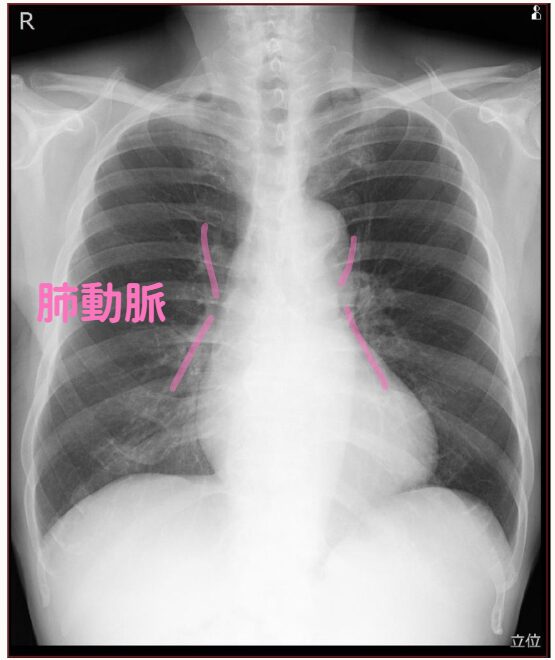

(6)肺動脈

肺動脈に関しては、この陰影が肺動脈ということを知っていると良いことがあります。

肺塞栓症は造影CTで診断するわけですが、レントゲンで何だか肺動脈が太い場合、

慢性の肺塞栓かも知れないし、何らかの肺高血圧かも知れません。

少し考えを広げるのです。